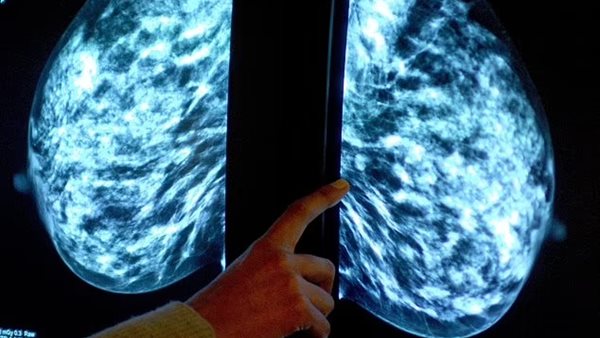

نمو الثدي خلال الحمل يزيد خطر الإصابة بالسرطان بين الأمهات الأكبر سنًا

اكتشف العلماء أن الأمهات الأكبر سنا اللاتي يلدن لأول مرة بعد سن الـ 35، لديهن مجموعات أكبر من الخلايا المتحولة في ثدييهن، والتي عادة ما تكون غير ضارة ولكنها يمكن أن تتحول إلى أورام، بنسبة تصل إلى 30%، وفقًا لـ صحيفة ديلي ميل البريطانية.

لكن الحمل، الذي يجعل الثديين أكبر حجما وجاهزا لإنتاج الحليب للرضيع، يزيد بشكل كبير من عدد خلايا الثدي، وربما بما في ذلك الخلايا الطافرة.

وذكرت الصحيفة أن اكتشاف مجموعات أكبر من الخلايا التي يحتمل أن تكون خطرة لدى الأمهات الأكبر سنا، يعني أن الأطباء يمكن أن يطوروا في المستقبل اختبارا لإخبارهن بخطر الإصابة بسرطان الثدي.